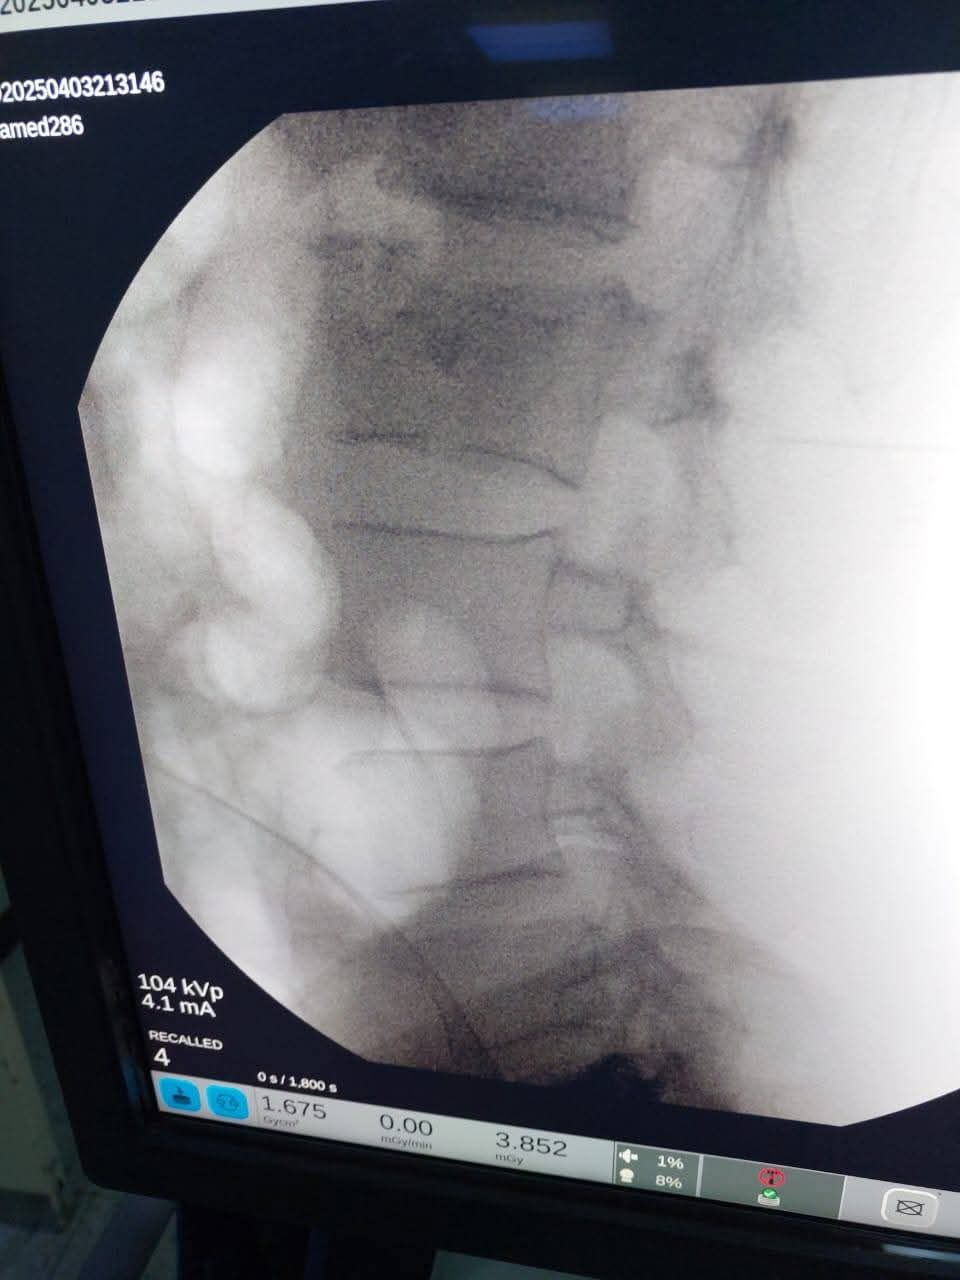

وفي سياق متصل، أكد الدكتور محمد بدران، مدير مديرية الصحة بدمياط، أن المستشفى استقبلت المريض بعد تعرضه لإصابة أثناء نزوله من القطار، حيث أصيب بكسر في الفقرات القطنية. وأوضح أنه تم إجراء الإسعافات الأولية للمريض، ثم تم تجهيز الحالة لإجراء العملية التي تكللت بالنجاح. تم تثبيت الكسر باستخدام المسامير والأعمدة الطبية، مع متابعة مستمرة لحالة المريض بعد إجراء الجراحة.